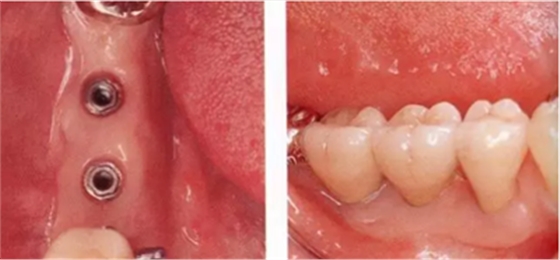

▲圖7-1,2

圖7-1 Type2-Class2的病例,頰側牙槽嵴基本沒有角化齦,需要增大角化齦的寬度。

圖7-2 第二次種植手術時佩戴愈合基臺后的狀態(tài)。舌側進行APF,頰側進行FGG以獲得角化齦。

圖7-3 第二次手術后3個月的狀態(tài)。頰舌側都有足夠的角化齦。

▲圖7-4

第二次手術后4個月的狀態(tài),口腔前庭較深,舌側角化齦寬度充足。

▲圖7-5

佩戴最終修復體后的舌側面照。有充足的角化齦,易于控制菌斑。